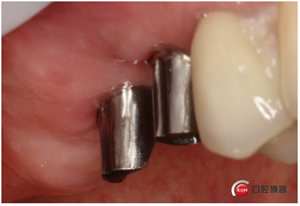

說(shuō)書的一張嘴,唱戲的跑斷腿,轉(zhuǎn)眼間半年過(guò)去了,見(jiàn)證時(shí)刻的奇跡到了!

試戴冠,看起來(lái)還不錯(cuò)哈,但我不滿意,大家看看有什么問(wèn)題?看看下頜那幾顆比較明顯。